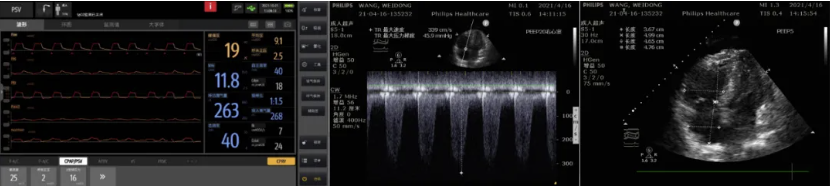

这是一名66岁男性患者的胸部CT对比,患者无明显诱因发热1月余,伴寒战,活动后呼吸困难加重,抗感染治疗效果不佳。

5天前,氧合指数降至64.5mmHg,建VV-ECMO后收入RICU。

可见,右心保护策略包括血流动力学和其他特定管理,跨肺压指导的机械通气策略可在实现肺保护的同时让肺休息,以此获得最优化的右心功能。